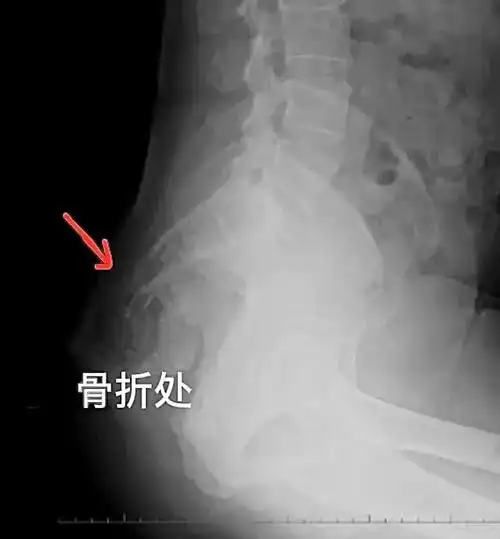

摔跤屁股疼莫轻视小心是尾骨骨折

上,在尾椎骨持续疼痛数天之后由医师评价发现有尾骨骨折裂伤的情况